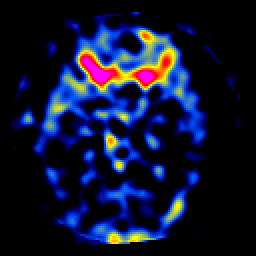

SPECT TL Study #7 -- Slice #22